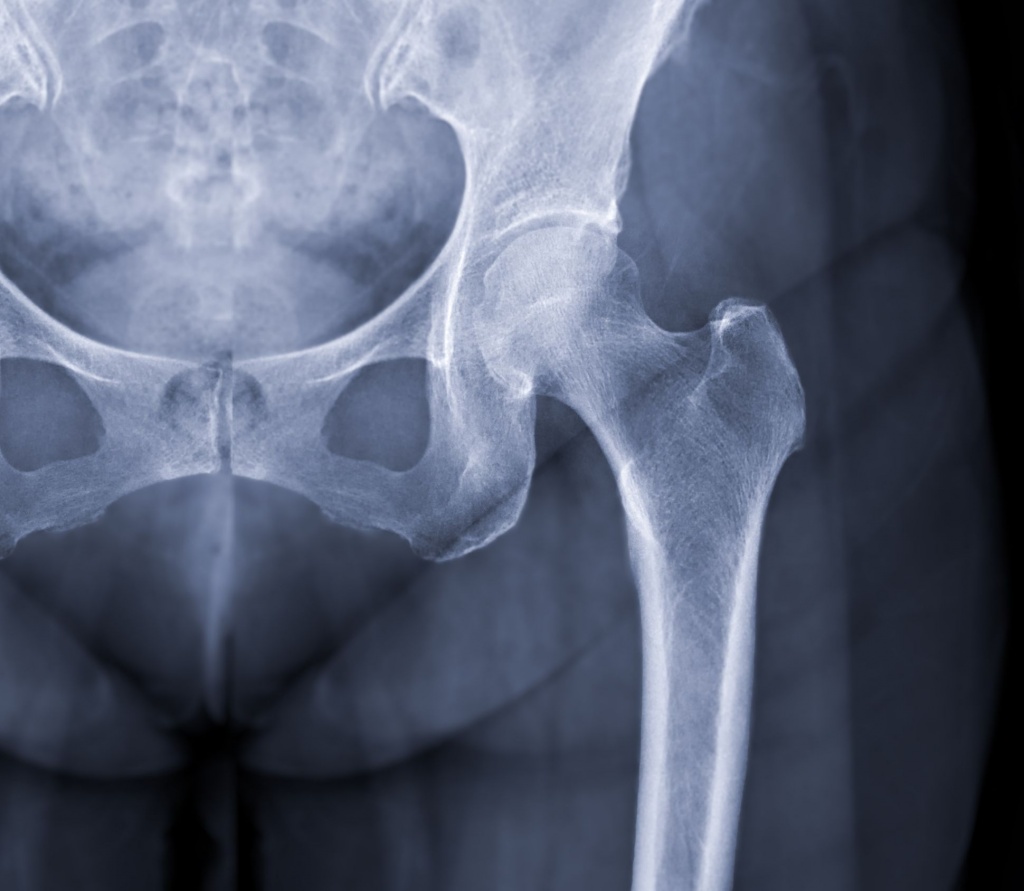

Кульшовий суглоб є одним із найбільших і найнавантаженіших суглобів людського тіла. Він забезпечує опору, рухливість та стабільність під час ходи, сидіння, підйому з положення сидячи. Будь-які зміни в цій ділянці швидко впливають на якість руху та самопочуття людини.

Рентген кульшового суглоба – це базове інструментальне дослідження, яке дозволяє оцінити стан кісткових структур суглоба, виявити дегенеративні, травматичні або анатомічні зміни та визначити подальшу тактику лікування.

Під час рентгенографії лікар може оцінити:

форму та положення головки стегнової кістки;

стан вертлюжної западини;

ширину суглобової щілини;

наявність деформацій;

ознаки артрозу кульшового суглоба;

наслідки травм, переломів або вивихів;

вроджені чи набуті анатомічні особливості.

Дослідження дозволяє об’єктивно підтвердити або виключити кісткові причини болю в ділянці кульшового суглоба.